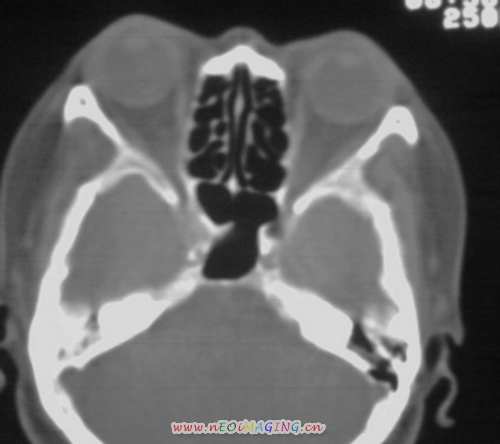

以下是引用随光逐影在2008-3-28 11:41:00的发言:[br]右侧蝶骨大翼骨质破坏,骨质破坏区内为软组织密度影填塞,右侧翼腭窝似有扩大,右侧乳突部分蜂房密度增高;疑鼻咽部肿瘤。建议:行鼻咽部ct扫描检查。另:右侧上颌窦黏膜下囊肿(或息肉)。

以下是引用jiangjing在2008-3-28 14:09:00的发言:[br]右侧蝶骨大翼骨质破坏,骨质破坏区内为软组织密度影填塞,右侧翼腭窝似有扩大,右侧乳突部分蜂房密度增高;疑鼻咽部肿瘤。建议:行鼻咽部ct扫描检查。另:右侧上颌窦黏膜下囊肿(或息肉)。